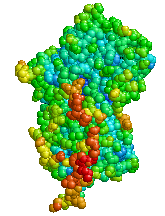

|

Structure of Alpha 1-antitrypsin | |